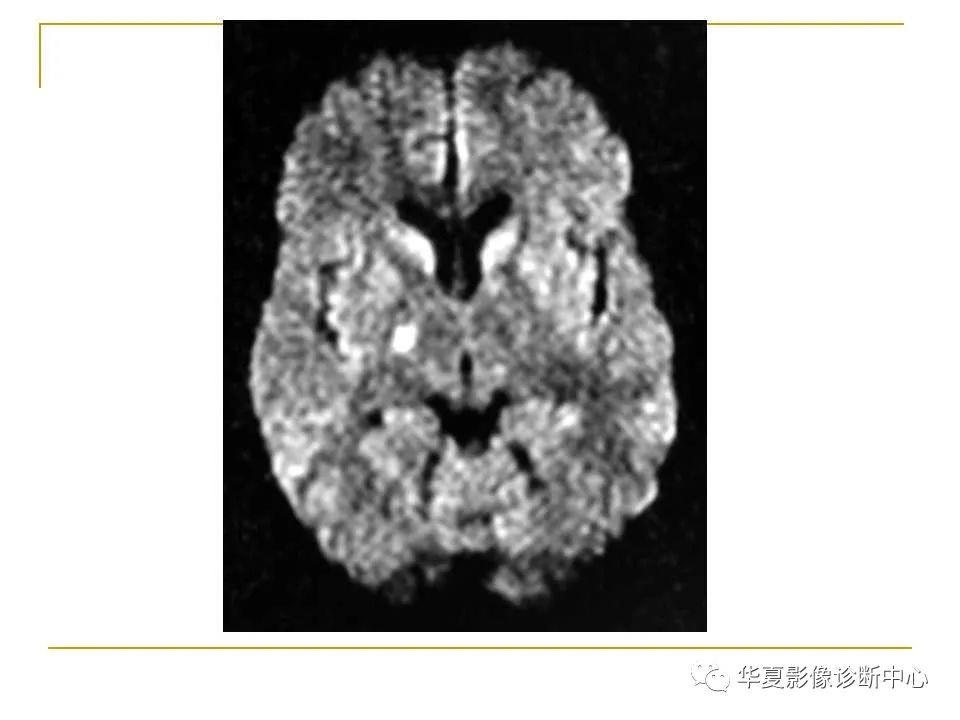

胼胝体解剖及病变大全